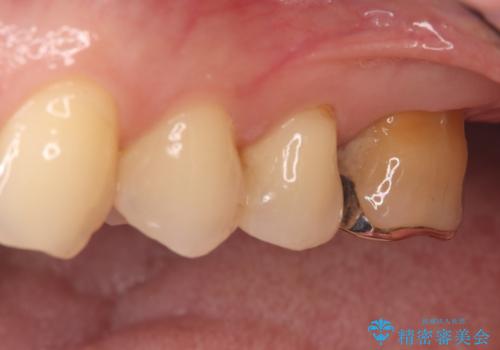

治療は、根管内の感染源を顕微鏡下で徹底的に除去・消毒する精密再根管治療から行いました。

根の状態が安定した後、金属を一切使用しないオールセラミッククラウンを装着しました。高い適合精度により二次感染のリスクを抑え、天然歯に近い透明感と耐久性を両立させています。根の違和感も解消され、機能・審美ともに健康な状態を取り戻しました。